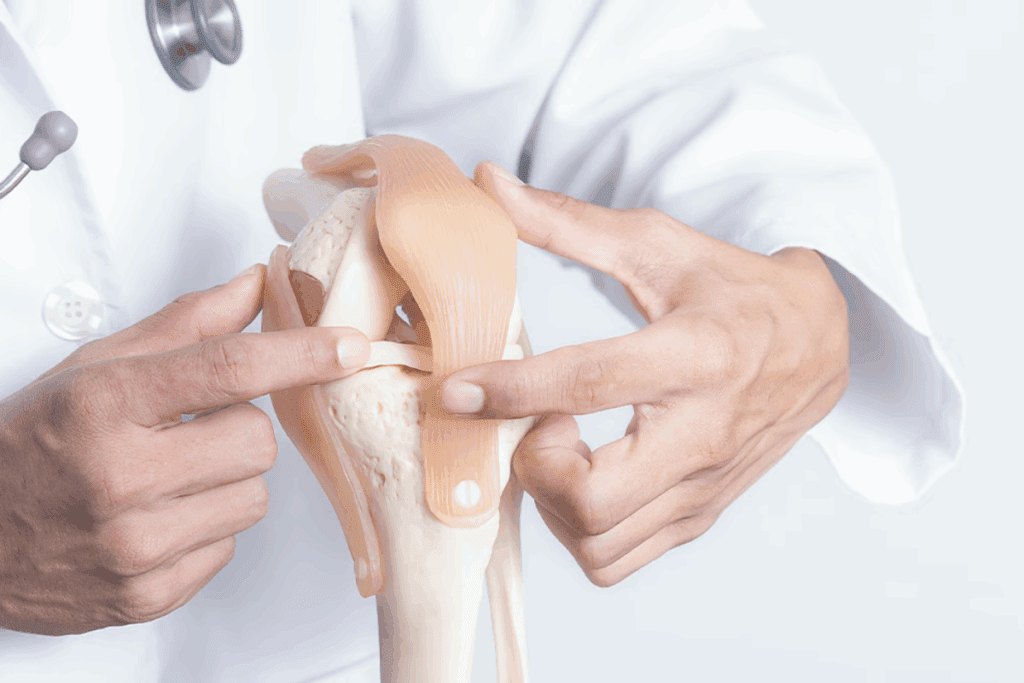

Hinge joints move in one direction, like a door opening. The elbow joint and knee joint are examples. They let us bend and straighten our arms and legs.

These parts work together to support our joints. For example, in the knee, ligaments keep it stable, tendons connect muscles to bones, and muscles help us bend and straighten.